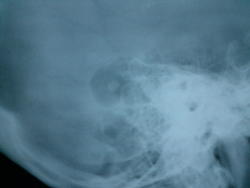

Этот "глаз" расположен кзади от углов Чителли обеих височных костей, так что ни под холестеатому, ни под фрезевое ложе не подходит. Варианты:

- предоставить нормальную прямую проекцию (для начала)

- прямое показание для снимков по Шюллеру и Майеру

- достать пациента и выяснить анамнез, можно и прощупать интересующие области

Без первых двух условий гадать можно много...